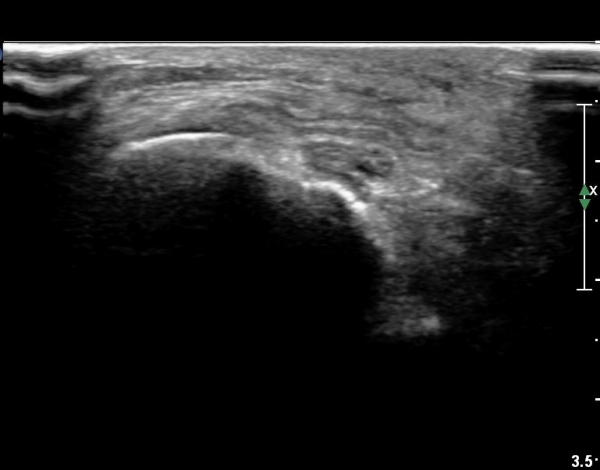

¹«¸­ ¿À±Ý ºÎÀ§ Ⱦ´Ü¸é°Ë»ç¿¡¼­ °æ°ñµ¿¸Æ Ç¥Ãþ¿¡ ºñ°ñ½Å°æ°ú °æ°ñ½Å°æÀÌ ºÐ¸®µÇ¾î °üÂûµÈ´Ù(»çÁø 1).